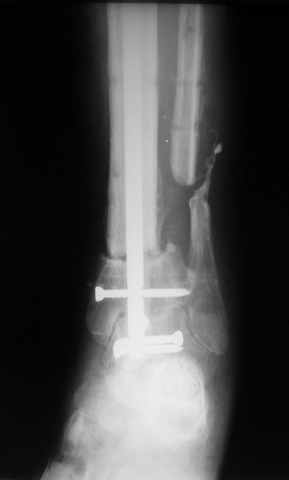

Ерсин, мы тоже имеем опыт такой фиксации. Подобную операцию за последние 3 года мы сделали трем пациентам. Снимки одного из них я прилагаю. К сожалению, ни в одном из этих 3-х случаев мы не получили удовлетворяющего нас результата. Очень трудно провести штифт, введенный антеградно ровно по центру таранной кости. Отсутствие подвижности между диафизом и дистальным отломком большеберцовой кости (после фиксации в аппарате в течение 1-2 мес) очень усложняет проведение штифта в центр блока таранной кости. Поэтому мы от этого пока отказались, и проводим штифт через пятку. При данном варианте фиксации подобных проблем не возникало ни разу.

Имя     : 1.jpg

Тип     : image/jpeg

Размер  : 15931 байтов

Описание: отсутствует

Url     : http://weborto.net:8080/pipermail/ortho/attachments/20081209/5d3bc875/attachment-0004.jpg